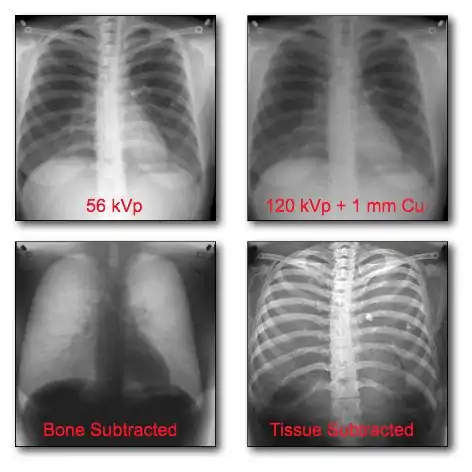

The application of DR technologies has also led the development of new imaging techniques, such as Digital Tomosynthesis and Temporal Subtraction, and to new forms of digital image processing, e.g. rib suppression in chest radiography[14] and Computer-Assisted Diagnosis (CAD)[15]. These topics however are beyond the scope of our considerations here.

Dual-Energy Imaging